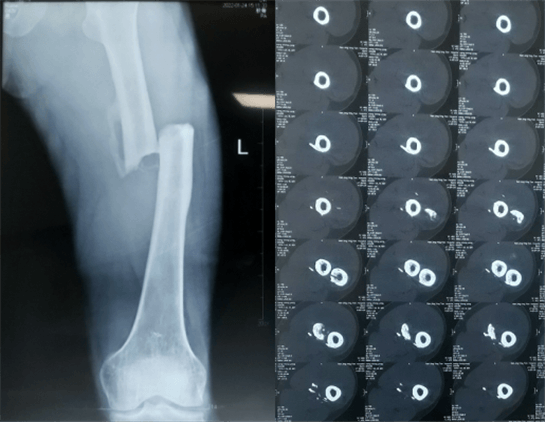

患者:男性,43歲,左股骨干骨折髓內(nèi)釘內(nèi)固定術(shù)

醫(yī)院:南京應(yīng)天骨科醫(yī)院

股骨是下肢的主要負(fù)重骨,有其特殊的解剖關(guān)系,周圍肌肉發(fā)達(dá),因此一旦股骨干骨折后如果治療不當(dāng),容易造成肌肉牽拉,導(dǎo)致畸形和功能障礙。治療股骨干骨折,必須遵循恢復(fù)肢體的長(zhǎng)度及力線,無(wú)旋轉(zhuǎn),盡量行以微創(chuàng),保護(hù)骨折局部血運(yùn),促進(jìn)愈合。髓內(nèi)釘對(duì)骨折的固定能夠達(dá)到較大的穩(wěn)定性和堅(jiān)固性,可以減少醫(yī)源性污染,減少軟組織分離及周圍血供破壞,有利于骨折早期愈合,是治療股骨干骨折的首要治療方法。

術(shù)前檢查